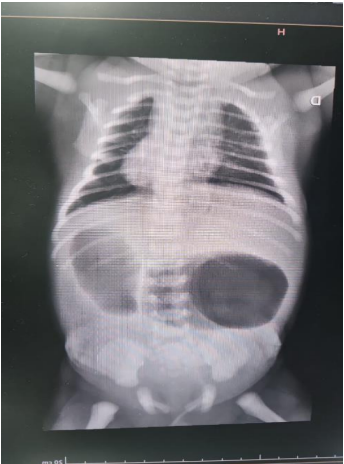

Considere o seguinte caso: recém-nascido de 32 semanas de gestação, com peso ao nascer de 1.545 gramas; polidramnia gestacional e ecocardiograma fetal com persistência do canal arterial e comunicação interatrial; portador de Síndrome de Down e sem outras malformações aparentes. Na sala de parto, tentou-se passar sonda nasogástrica, porém sem progressão. Encaminhado para unidade de terapia intensiva devido à prematuridade. Evoluiu com distensão abdominal e resíduo gástrico bilioso. A radiografia de tórax e abdome é mostrada na Figura 1 a seguir. Com base nessas informações, a patologia cirúrgica que pode estar presente é:

Figura 1